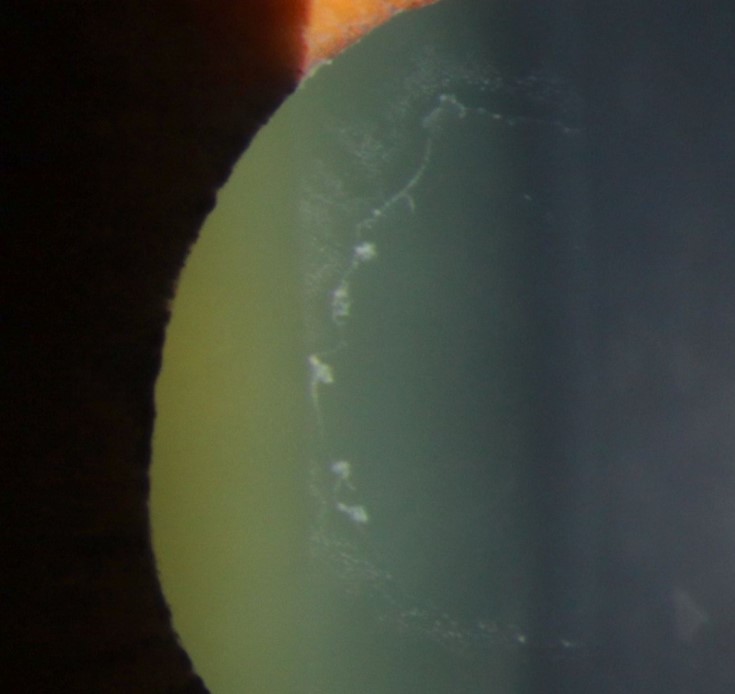

Image 2 shows pseudoexfoliative material on the pupil margin. This is often associated with loss of pupillary ruff as you can see in the photograph. Retroillumination can be particularly useful to observe transillumination defects at the pupil margin.